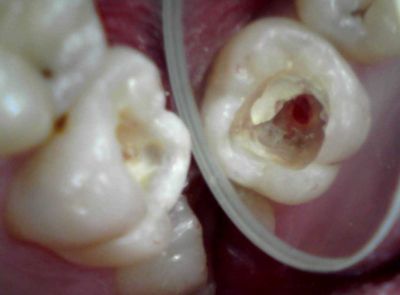

神経がこんな感じに腐ってたらもう、取るしか方法ないですわな。

生活歯髄切断法ていうのは、例えばこんな齲蝕の深い症例で、

歯冠部の歯髄だけ除去して、根の部分の歯髄を残す治療法です。